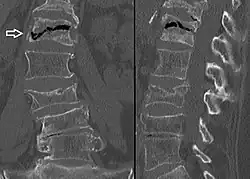

The intravertebral vacuum cleft sign (at white arrow) is a sign of avascular necrosis. Avascular necrosis of a vertebral body after a vertebral compression fracture is called Kümmel's disease.[20] -